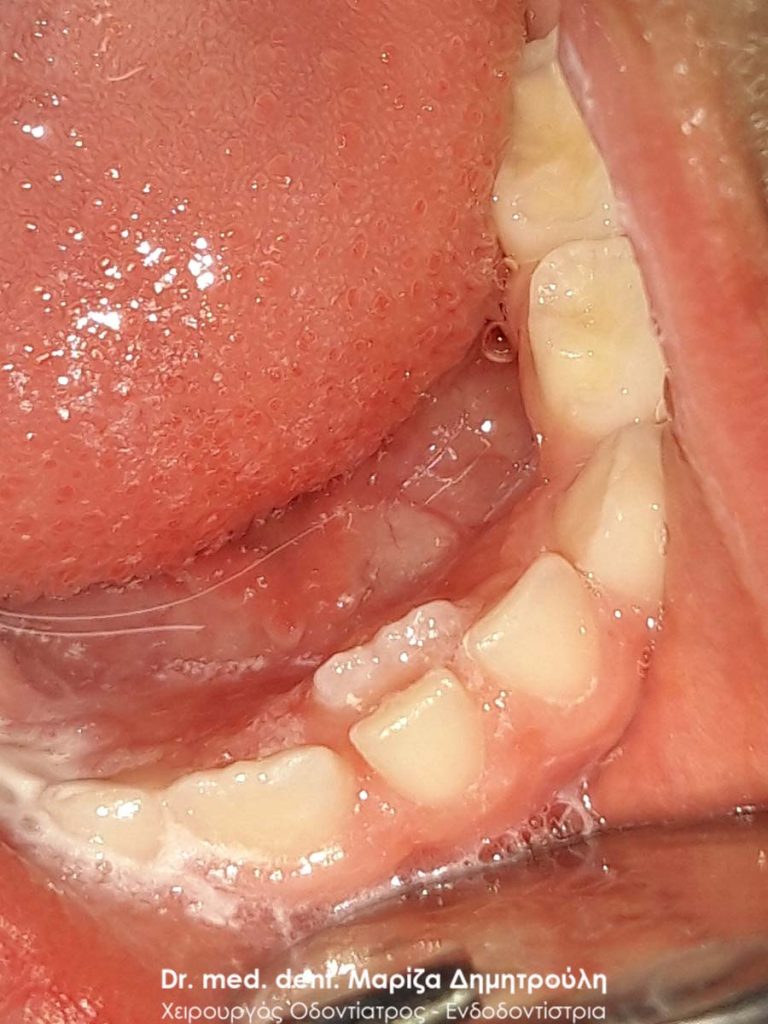

Διπλό παιδικό δόντι

Σε πολλά παιδάκια παρατηρείται να εμφανίζεται το μόνιμο δόντι πάνω ή πίσω από το αντίστοιχο νεογιλό δόντι. Στα περιστατικά αυτά το νεογιλό δόντι παραμένει στη θέση του, με αποτέλεσμα το μόνιμο δόντι να μην έχει χώρο να πάρει τη σωστή θέση του στο παιδικό στόμα. Τότε οι γονείς συχνά τρομάζουν οτι κάτι περίεργο συμβαίνει στο στόμα του παιδιού τους. Στην ουσία όμως δεν θα πρέπει να ανησυχούν, αφού αυτό που απλά χρειάζεται,είναι να απευθυνθούν στον παιδοδοντίατρο για να αφαιρέσει το παιδικό δοντάκι. Στη συνέχεια στην πλειονότητα των περιστατικών το μόνιμο δοντάκι παίρνει τη σωστή θέση του στο στόμα χωρίς να χρειαστεί η παρέμβαση του ορθοδοντικού. Σε άλλες περιπτώσεις πράγματι το παιδί μπορεί να χρειαστεί ορθοδοντική θεραπεία, αλλά συνήθως συντρέχουν και άλλοι παράγοντες.